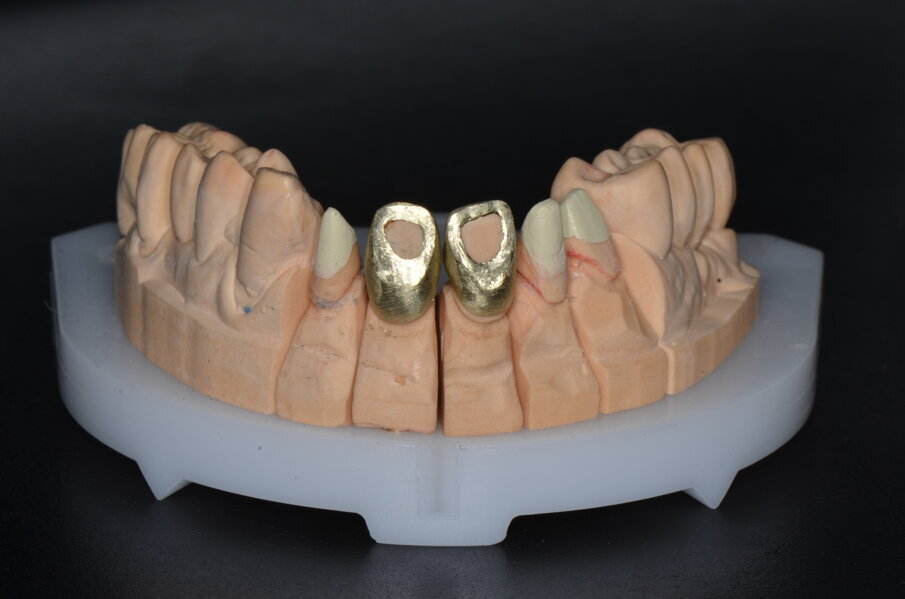

Le corone definitive, come precedentemente descritto, vengono costruite con tecnologia CAD/CAM per una sottostruttura in zirconia di cui viene verificato l’adattamento e ricercata la precisione seguendo gli stessi criteri noti per una prova fusione di una struttura metallica (Figg. 23-29). Dopo la prova le strutture vengono inviate in laboratorio per la stratificazione della ceramica.